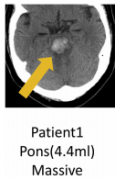

原发性脑干出血的外科治疗案例

原发性脑干出血(脑干出血)是一种预后不良的灾难性事件。在东亚...